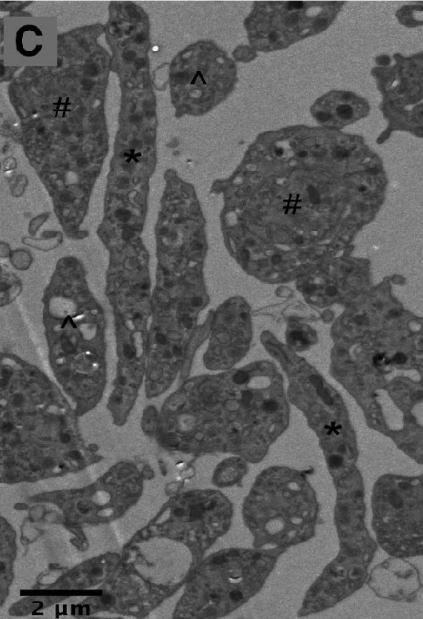

(脑补一下,动画里巨核细胞身上蹦出一个个血小板的样子,好家伙) 电子显微镜下的前血小板(#和*标注)与血小板(^标注) | 图源:Machlus K R, Italiano J E.

新生成的前血小板会立刻穿过血窦壁进入血管内,其内的微管还会继续延伸,促使它们再次分裂,形成我们熟悉的血小板。 来我们回顾一下刚刚讲的血小板的起源 | 图片翻译自:Machlus K R, Italiano J E.